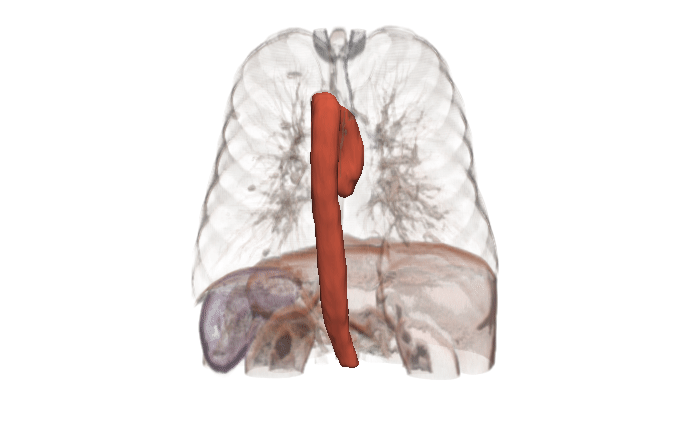

In many cases, the computational domain is derived from patient-specific anatomy. It starts with a medical image: MRI, CT, OCT, IVUS, etc. This provides a 3D volume from which a specific anatomy must be segmented. The segmentation, also known as a label map, is essentially a subset of voxels that are considered part of the anatomy. It is a volumetric mask that represents the object to be modeled (a heart, a vessel, an airway, etc.).

Before generating a 3D volume mesh for CFD, the segmentation undergoes preprocessing for refinement including ensuring a watertight mesh can be generated for simulation and face/surface labeling. The algorithms for doing this are often anatomy dependent, and the identification of faces for boundary conditions often relies on custom scripts. When dealing with many medical images, both manual segmentation and custom scripting can quickly become expensive and time consuming.

SimVascular is an open source software package that provides an end-to-end pipeline for cardiovascular CFD modeling. It is specialized for cardiovascular applications and less general-purpose than 3D Slicer, but it is an exception to the “no all-in-one solutions” comment above. SimVascular provides within a single environment tools for segmentation, model construction, and finite element solvers for cardiac modeling and vascular hemodynamics.

Kitware can provide end-to-end support for CFD companies who are expanding into the medical domain. Our open source platforms (3D Slicer, ITK, Pulse, ParaView, CMB) are flexible and customizable for the pre-processing needs and workflow management of CFD problems. Our expertise includes integration of simulation models into software, custom AI models for automated segmentation, custom algorithm development for cleaning up segmentation topology and geometry, and visualizing CFD output.